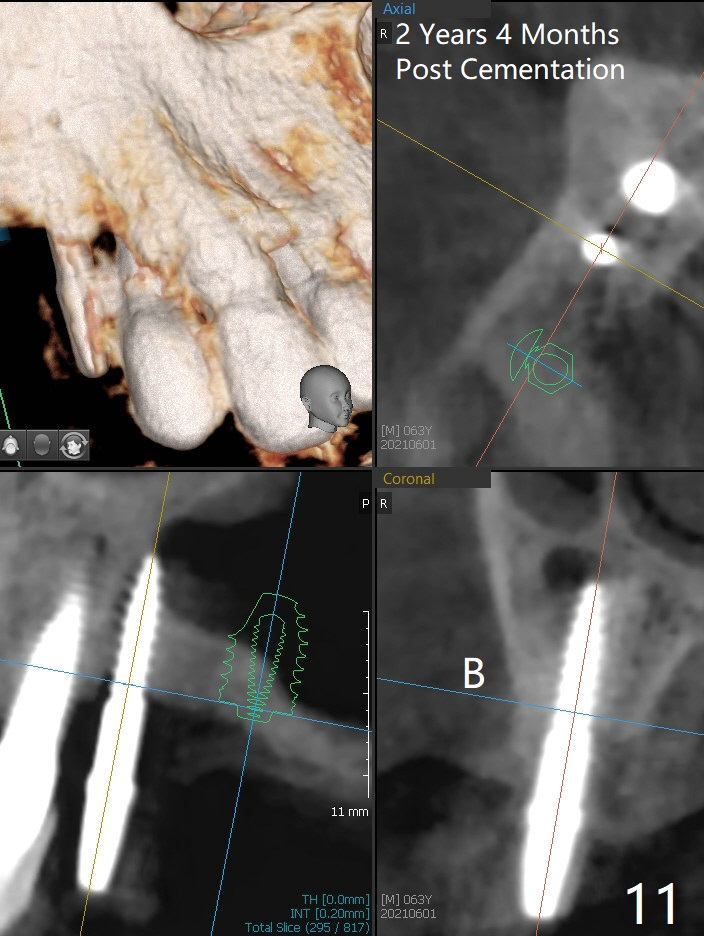

The osteotomy gap at #4 disappears 3.5 months post implant removal with bone graft; the mesiodistal space is 6.6 mm (Fig.1). Incision confirms disappearance of the osteotomy gap. A new osteotomy is established for 10 mm (Fig.2). A 2.5x10(4) mm 1-piece implant is placed with <50 Ncm; since the trimmed implant threads at #5 are exposed (Fig.3), Vanilla graft with Osteogen is placed mesial and distal to the new small implant (Fig.4 *). There is no bone loss 3.5 months postop (Fig.5,6). After cementation of the crown (Fig.7 C) with the thin abutment (*), the patient feels that the crown has mobility. The crown in fact has no clinical mobility; it cannot be removed. After occlusal equilibrium, the patient does not feel the same. The thin 1-piece implant must flex under heavy occlusion. The patient is a bruxer. There is no crestal bone resorption 4 months post cementation (8 months post cementation, Fig.8,9). There is no sign of periimplantitis anymore. The implant remains mobile and symptomatic (chewing pain) 14 months post cementation (Fig.10). There is no bone loss 2 years 4 months post cementation (Fig.11).